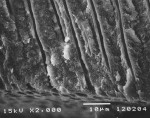

The SEM images in Figure 3 show close-up views of cross-sections of untreated (Figure 3a) and Q-treated (Figure 3b) dentin. The coherent nature of the 2-µ to 3-µ thick surface layer on this part of the treated dentin was clearly seen, and bonding of deposited mineral with the dentin surface was apparent.

The EDX elemental analysis of the professional desensitizer-treated surface is consistent with the presence of ACP or HAP together with potassium, phosphate, and chloride ions. Based on the mineral’s coherent nature, what is observed in the SEM seems to be HAP, formed from hydrolysis of ACP, which was likely to have been initially deposited. No protein was detectable in the surface as shown by the lack of carbon in the EDX. This demonstrated that the analyzed portion of the dentin surface was well covered by the deposited mineral.

This study’s finding of calcium phosphate deposition by the professional desensitizer was similar to that found by Tung et al who determined sequential applications of calcium and phosphate solutions to dentin disks produced a layer of ACP and resulted in significant reductions of as much as 99.9% in dentin permeability.12,16 However, examination of the SEMs indicated the deposit formed in the authors’ study was more crystalline than that formed on the dentin in studies by Tung et al. As previously mentioned, ACP is unstable in the presence of moisture and known to transform into other less soluble crystalline calcium phosphate salts. Fluoride reportedly catalyzes the transformation of ACP to apatitic mineral.10 Depending on how soon after treatment the SEM was obtained, ACP, HAP, or mixtures of the two could be present. In this study, it appeared the mineral had largely transformed into the more crystalline HAP mineral. The SEM of the dentin cross section shows a highly coherent nature and a strong bond with the dentin surface.